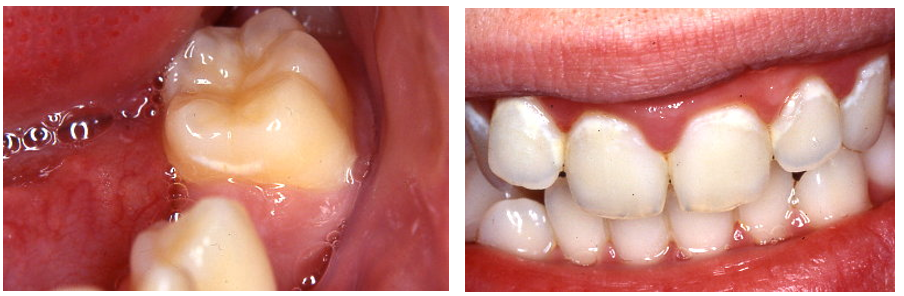

What is the aetiology of an eruption cyst?

* Epithelial source; reduced enamel epithelium. Soft tissue equivalent of a dentigerous cyst

* Produce a round, soft, blue cyst over the gingivae

* They occur when the dental follicle separates from the erupting tooths crown in the soft tissue

* Can relf resolve or require a small excision to drain the fluid and allow the tooth to erupt

* No radiograph is required